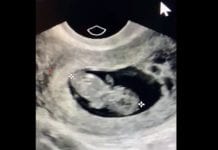

“Mój najmłodszy pacjent został poczęty ” 7 tygodni temu”

Mój najmłodszy pacjent - taki Twitt zamieściła lekarka Grazie P Christie MD i dodała

"Najbardziej zwyczajna rzecz na świecie jest jednocześnie najbardziej cudowna"

My youngest patient...